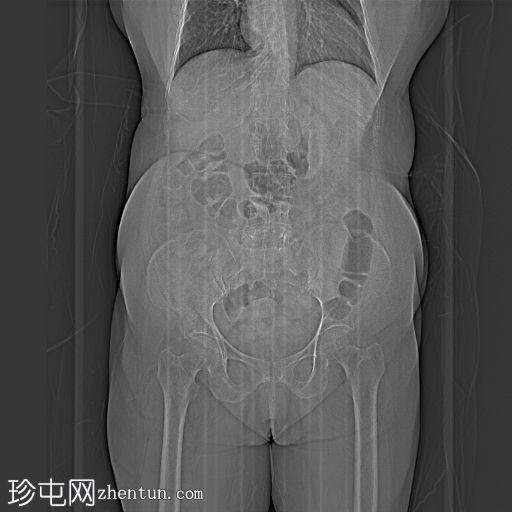

3.png

轴位增强扫描

门静脉期

左侧髂总静脉延续为左侧髂外静脉。左侧髂内静脉未汇入左侧髂总静脉,而是汇入右侧髂内静脉,并在 S1 椎体水平跨越中线。

左肾发育不全,左肾动脉缺如,左侧肾上腺呈平卧位征。

左侧输尿管远端三分之一处呈盲端扩张,异位开口,可能位于阴道穹窿。